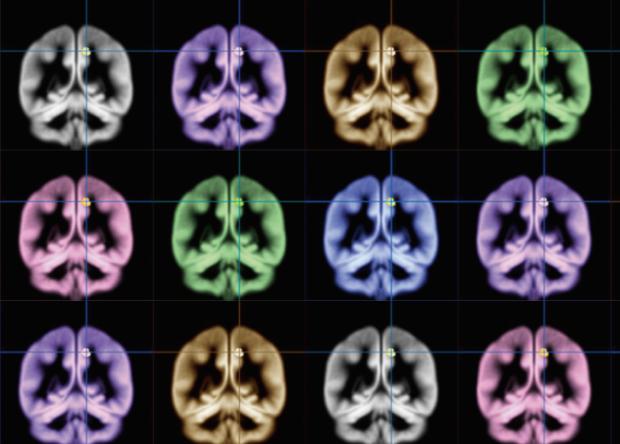

Используя структурную МРТ, ученые получили изображения мозга всех участников исследования. Статистический анализ показал, что уровень счастья коррелирует с количеством серого вещества в одной области правого полушария – внутренней части теменной коры (прекунеусе). Ранее ученые с помощью МРТ выяснили, что возникновение у человека счастливых эмоций сопровождается активацией теменной коры головного мозга.